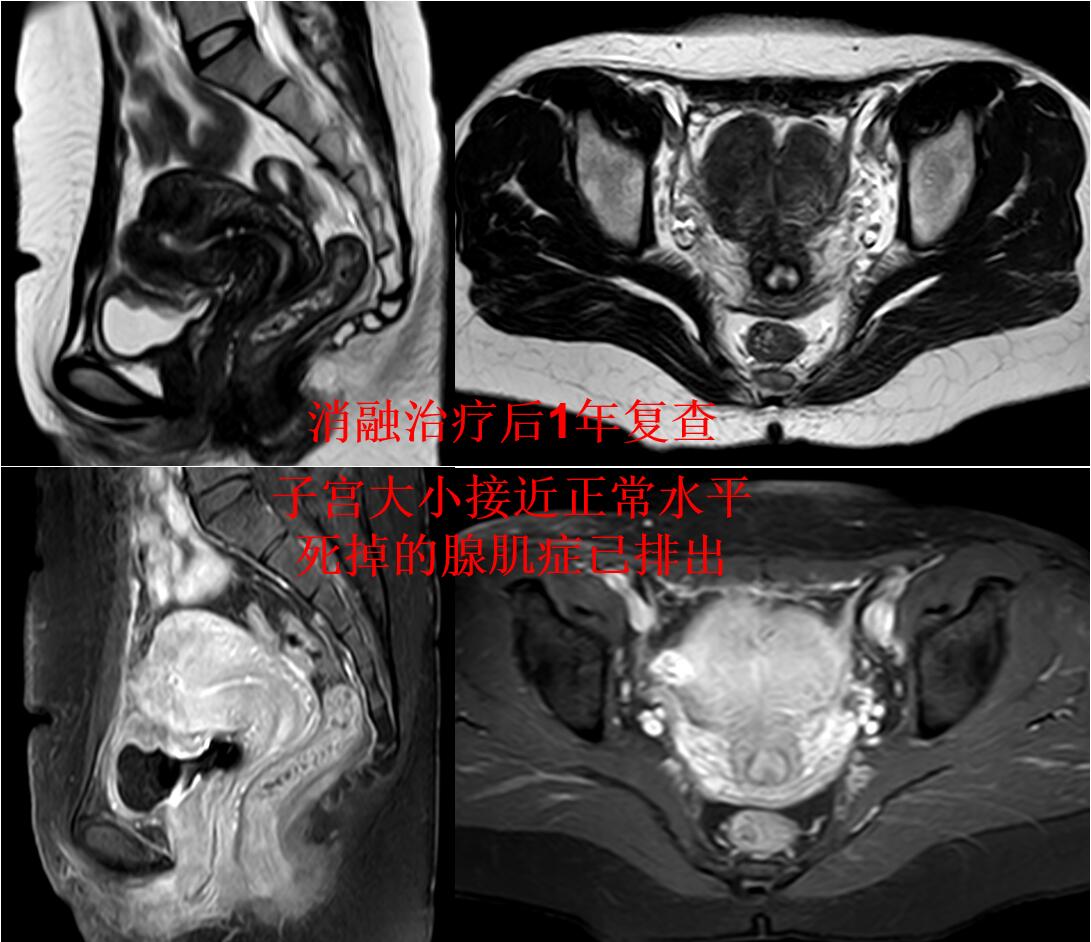

门诊磁共振检查:子宫明显增大(10.8*9.2*8.7cm3),子宫腺肌症,以宫底及后壁明显(如下图)。

介入微创消融治疗后无明显痛经,3个月后复查磁共振显示:子宫腺肌病病灶灭亡,子宫缩小(如下图)。

介入微创消融治疗后1年痛经没法复发,复查磁共振显示:子宫大小恢复正常,腺肌症灭亡吸收排出(如下图)。